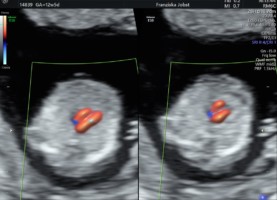

Ultraschalldiagnostik 12-14. SSW Erst-Trimesterscreening (NT-Mesung):

Mit Hilfe des Ersttrimesterscreenings (ETS) ist schon in der 12.-14. SSW durch die Beurteilung der Nackenfalte , des Nasenbeins und weiterer sonographischer Parameter (Ductus venosus, Trikuspidalklappe am Herzen etc.) sowie einer Blutentnahme (PAPP-A und freies ß HCG= plazentare Hormone) eine Risikoanalyse für das wahrscheinliche Auftreten einer Chromosomenstörungen Trisomie 21, Trisomie 13 oder Trisomie18 möglich. Die Erkennungsrate der Untersuchung beträgt ca.90-95% mit einer Falsch-Positiv-Rate von 2,5-5%.